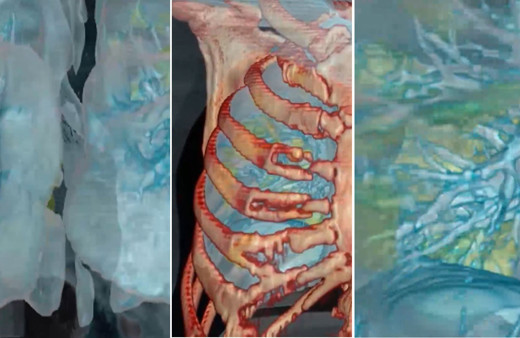

Akciğer